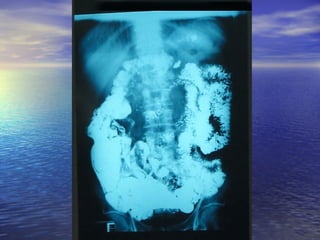

• 1.- Calibre de la luz intestinal1.- Calibre de la luz intestinal

• 2.- Contornos Superficie de mucosa2.- Contornos Superficie de mucosa

• 3.- Grosor de la pared de la mucosa3.- Grosor de la pared de la mucosa

• 4.- Desplazamiento de asas4.- Desplazamiento de asas

• 5.- Floculación, segmentación,5.- Floculación, segmentación,

obstrucciónobstrucción (Yeyuno imagen = pluma de(Yeyuno imagen = pluma de

aves)aves)

(ileon imagen = pila de monedas)(ileon imagen = pila de monedas)

Transito IntestinalTransito Intestinal Parámetrospara analizarParámetros para analizar • 1.- Calibre de la luz intestinal1.- Calibre de la luz intestinal • 2.- Contornos Superficie de mucosa2.- Contornos Superficie de mucosa • 3.- Grosor de la pared de la mucosa3.- Grosor de la pared de la mucosa • 4.- Desplazamiento de asas4.- Desplazamiento de asas • 5.- Floculación, segmentación,5.- Floculación, segmentación, obstrucciónobstrucción (Yeyuno imagen = pluma de(Yeyuno imagen = pluma de aves)aves) (ileon imagen = pila de monedas)(ileon imagen = pila de monedas)